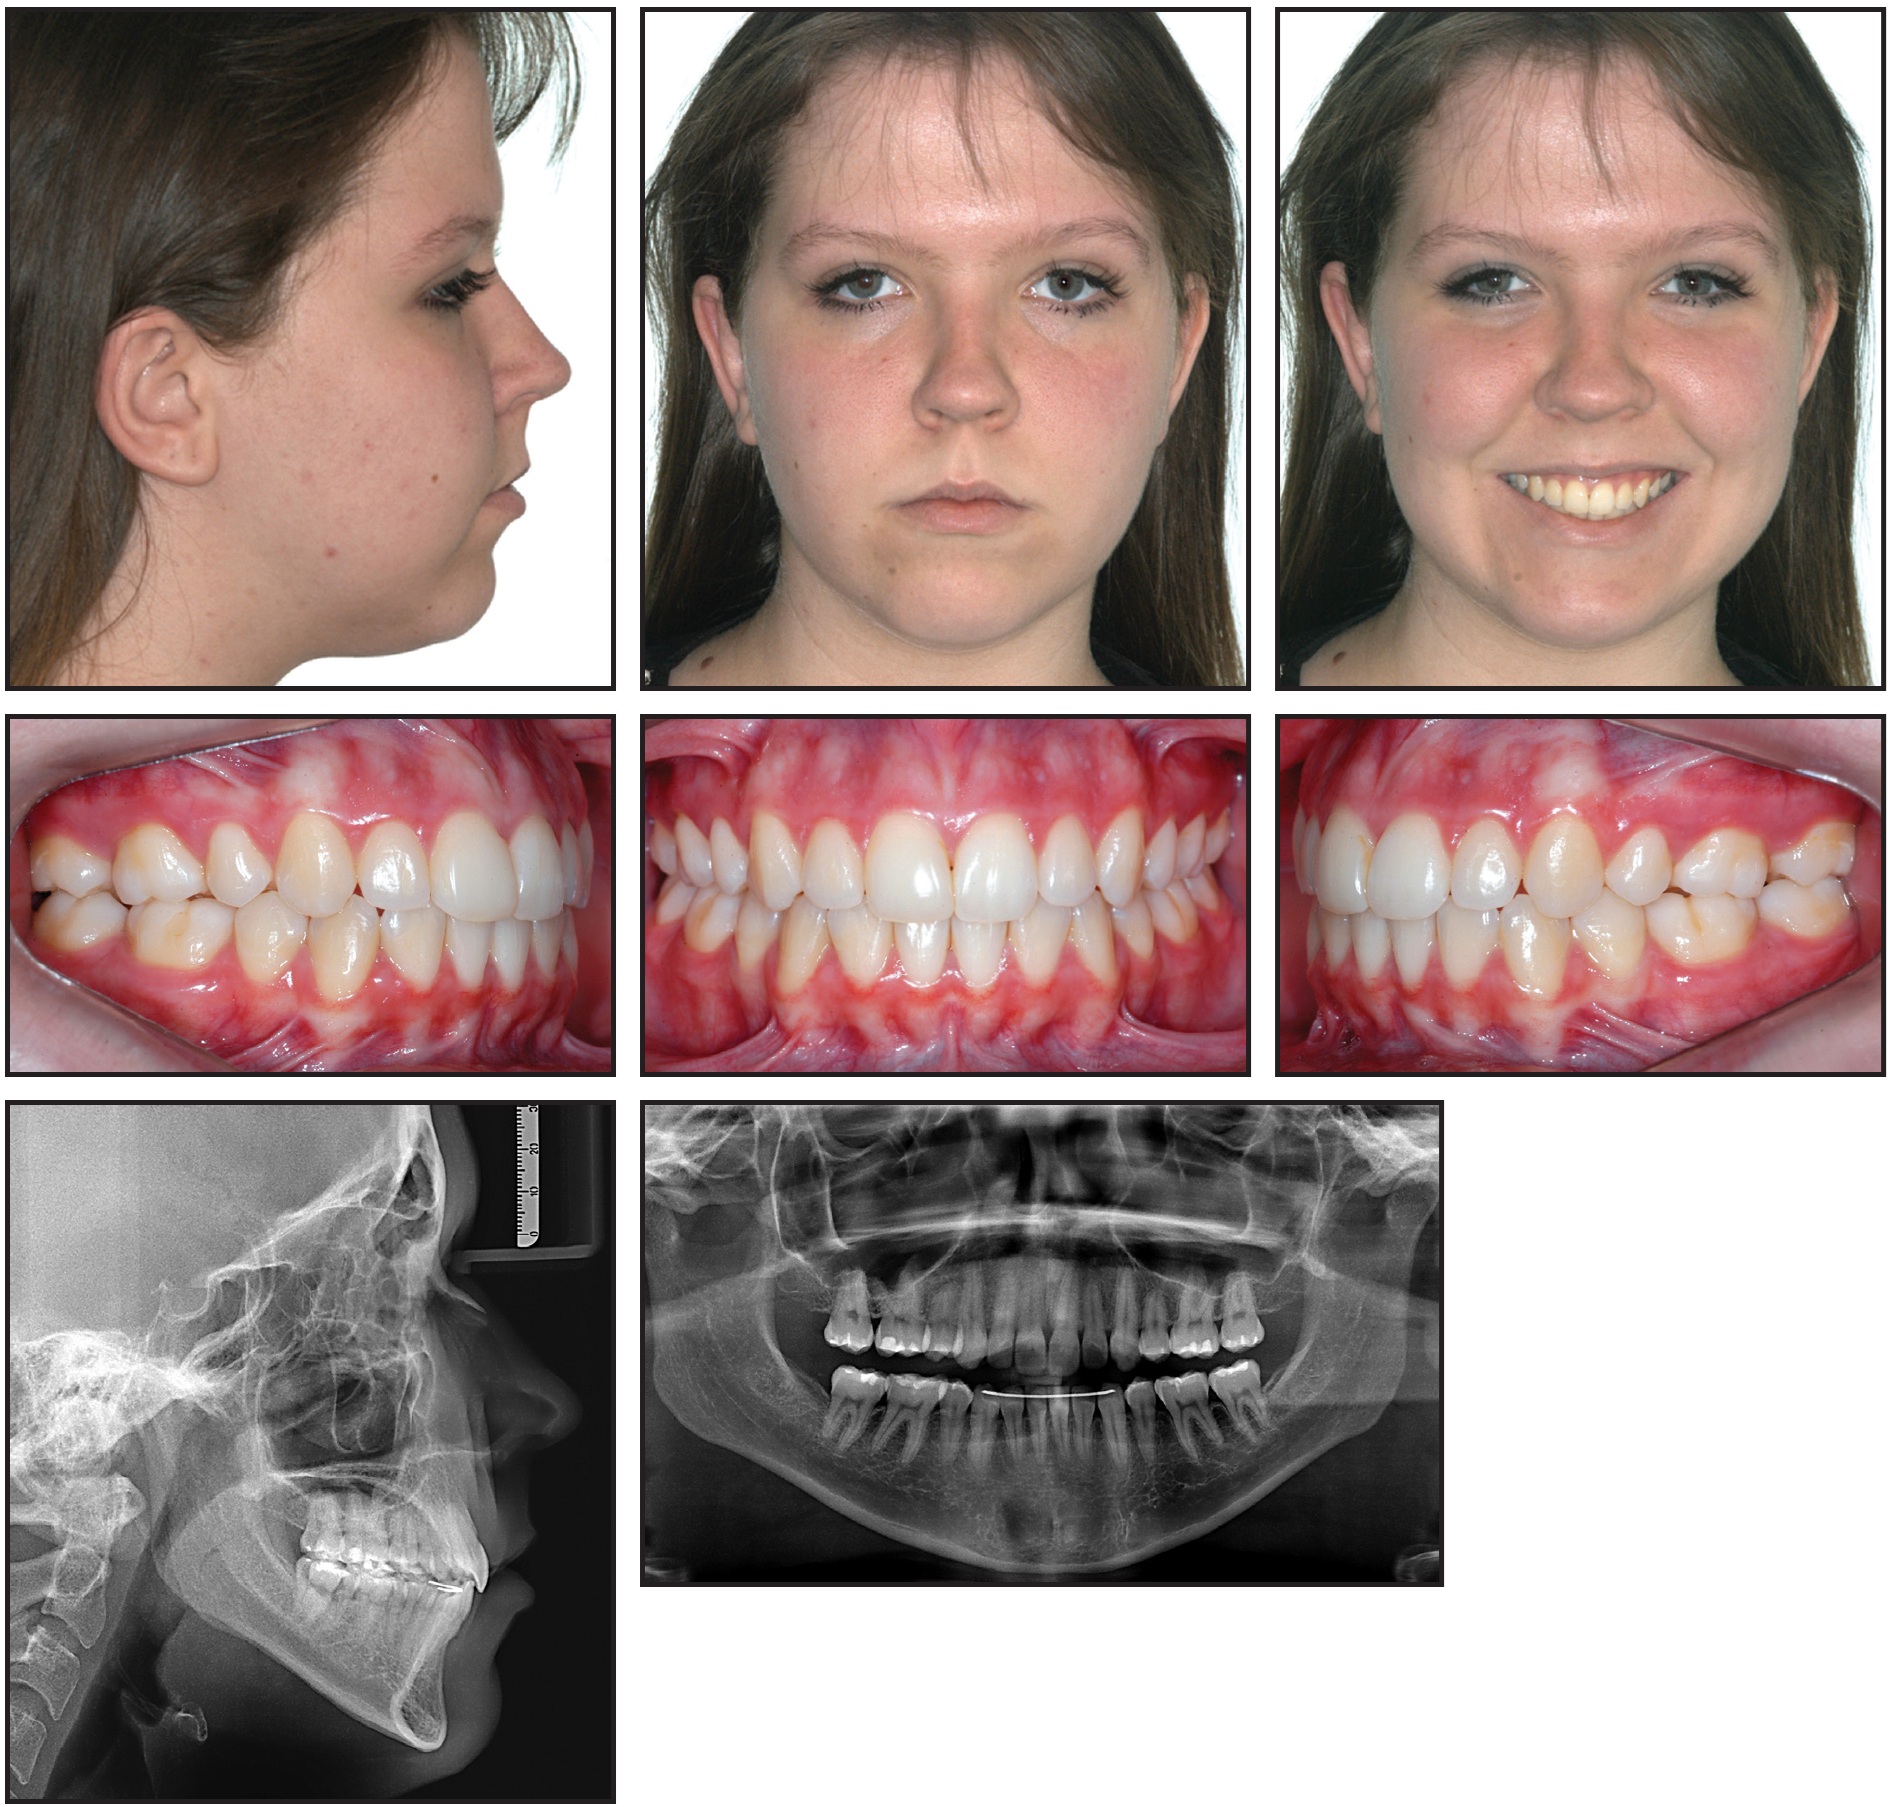

Fig. 3 Patient at start of Phase II, 36 months after Phase I completion.

Phase II was initiated 36 months after the completion of Phase I (Fig. 3).

An orthopedic device was used together with a combination-pull headgear to control vertical mandibular growth. This extraoral traction reduced the anteroposterior maxillomandibular discrepancy by promoting counterclockwise rotation of the mandible and restricting horizontal growth of the maxilla (Table 1).

After extraction of the upper first premolars and lower second deciduous molars on both sides, corrective orthodontic treatment was initiated with standard .022" × .028" edgewise appliances. Leveling and alignment occurred over 16 months on a sequence of .014" to .020" stainless steel archwires. To close the extraction spaces, looped .018" × .025" and .019" × .025" stainless steel archwires were used to retract the upper canines and incisors and the lower premolars, canines, and incisors. The patient wore the headgear nightly during this phase, which took 23 months. To improve intercuspation in the final stages, Class II intermaxillary elastics (¼") and vertical elastics (3⁄16") were worn bilaterally, along with intermaxillary elastics (¼") in the anterior region.

The total time of the corrective phase was 39 months (Fig. 4).

Fig. 4 Patient after 39 months of Phase II treatment.